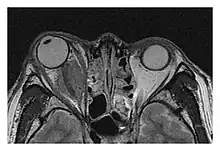

Mass lesion around the right optic disc in a 44-year-old man with IgG4-related ophthalmic disease and a serum IgG4 of 599 mg/dL.[1] (T2-weighted MRI) | |